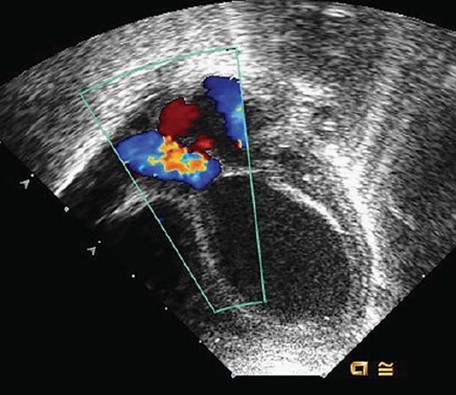

Chapter 172: Environmental Exposures and Health in Rudolph's Pediatrics, 23e stresses that the genome of developing fetuses are more susceptible to these environmental factors. Exposure to these pollutants pose a much higher risk to unborn infants (Figure 172-3). The chapter also elaborates on different toxic pollutants such as Cadmium and Polycyclic Aromatic Hydrocarbons.

Figure 172-3: Kline MW. Rudolph's Pediatrics, 23e; 2018.